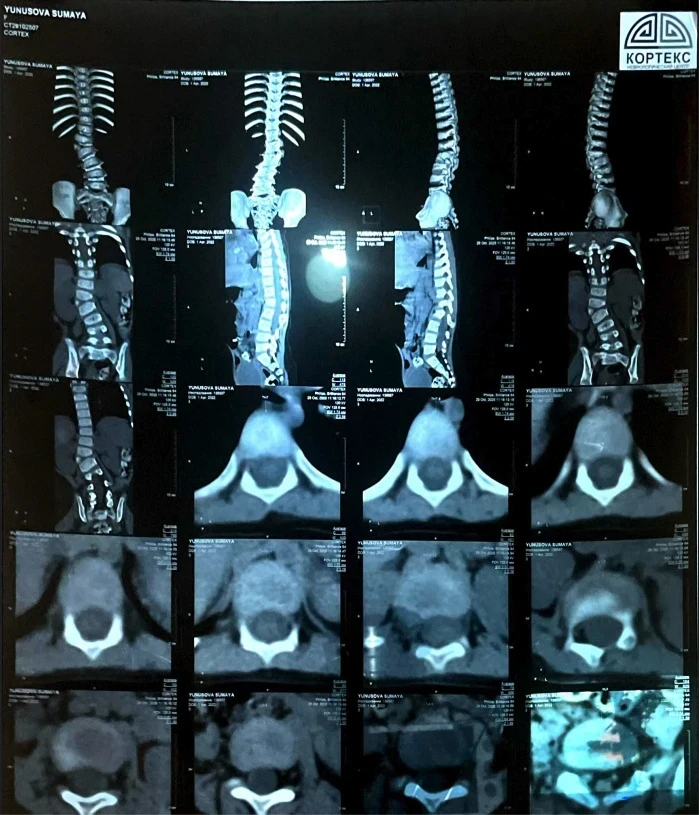

У девочки выявили сколиоз сложной формы, что вызывает у неё затруднения при ходьбе и беге, и она вынуждена проводить большую часть дня в сидячем или лежачем положении.

«Узнав, что ничего не помогает, мы обратились за консультацией к турецким профессорам. Они заявили, что единственный выход — операция, и чем быстрее она будет проведена, тем лучше для роста и развития Сумаи. Кроме того, мы узнали, что у неё есть лишняя кость на позвонке, что также является последствием сколиоза», - сообщает мама.

Сколиоз уже вызвал асимметрию тела, у Сумаи одно плечо ниже другого, а одна нога короче.

«Мы не знали, что сколиоз может привести к таким серьёзным последствиям, пока не столкнулись с этим сами. Мы проходили обследования, стараясь, чтобы дочь росла и развивалась нормально. Но о том, что искривление позвоночника может сдавливать внутренние органы и вызывать сильные боли, мы даже не подозревали. Поэтому нам нужно спешить с операцией», - добавляет Мадина.